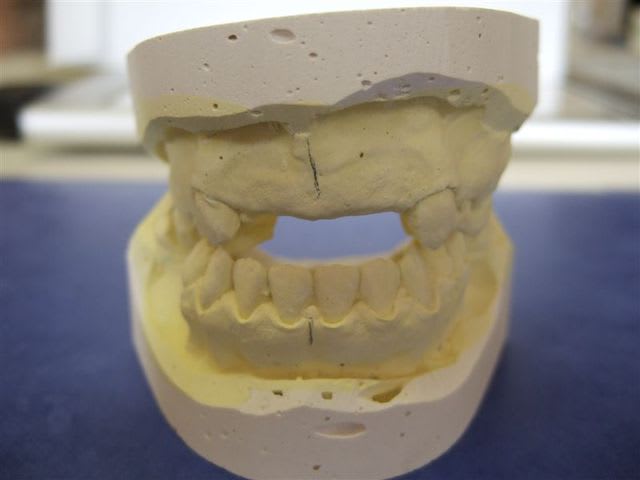

Moulages avant extractions